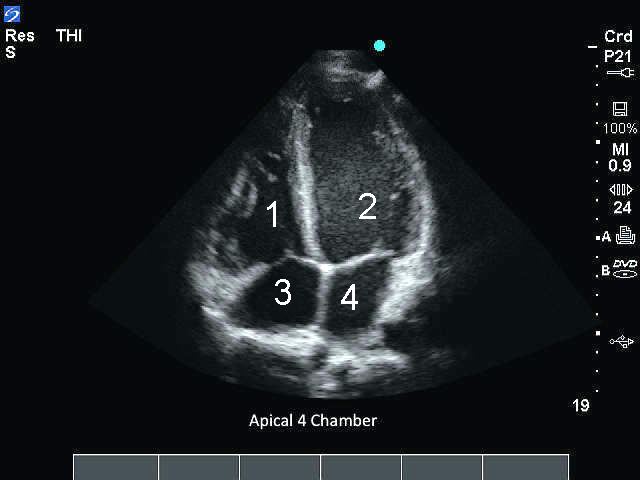

M-Turbo:心尖4室画像

M-Turbo:心尖4室

右心室 (RV)

左心室(LV)

右心房(RA)

左心房(LA)